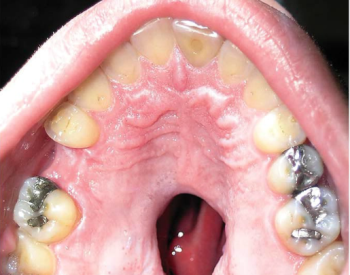

Dentista fica chocado com o que vê dentro da boca de paciente e alerta